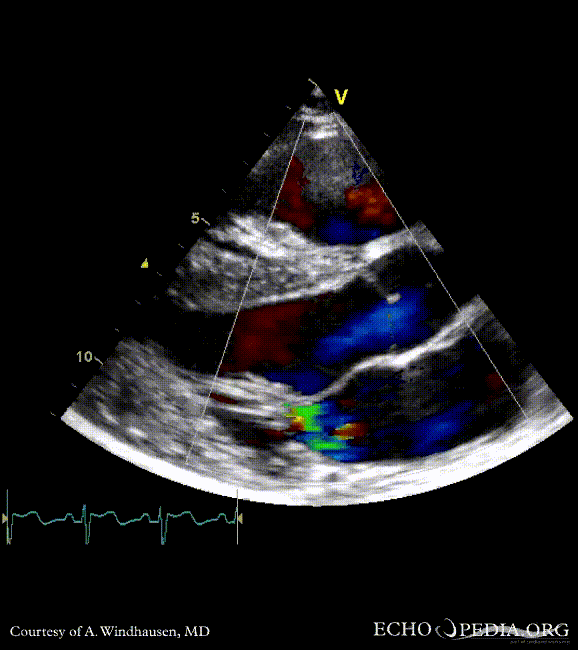

Severe Hypertrophic Cardiomyopathy (HCM)

Case description: Severe Hypertrophic Cardiomyopathy (HCM)

Courtesy of: A. Windhausen, AMC, The Netherlands

A2CH view A4CH view